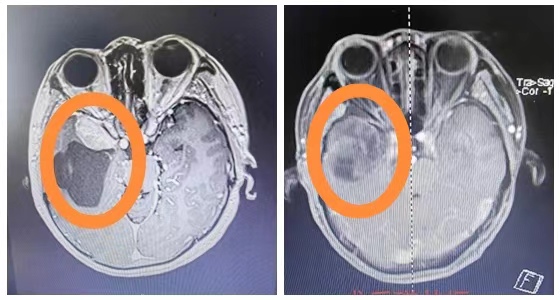

湘雅常德医院神经外科团队为李女士完善了相关检查,发现李女士右侧颞叶囊实性占位性病变,实性成分约32*19mm大小,囊性成分约74*53mm大小。

“李女士的这种情况,我们考虑为蝶骨嵴脑膜瘤,是颅内常见肿瘤之一。因为肿瘤的膨胀性生长,患者往往以头痛为首发症状,依肿瘤部位不同,可能出现视力、视野、嗅觉或听觉障碍及肢体运动障碍等,治疗手段主要是手术切除,但颅底肿瘤手术风险大。李女士现在的情况,手术刻不容缓。”神经外科主任袁贤瑞教授介绍道。